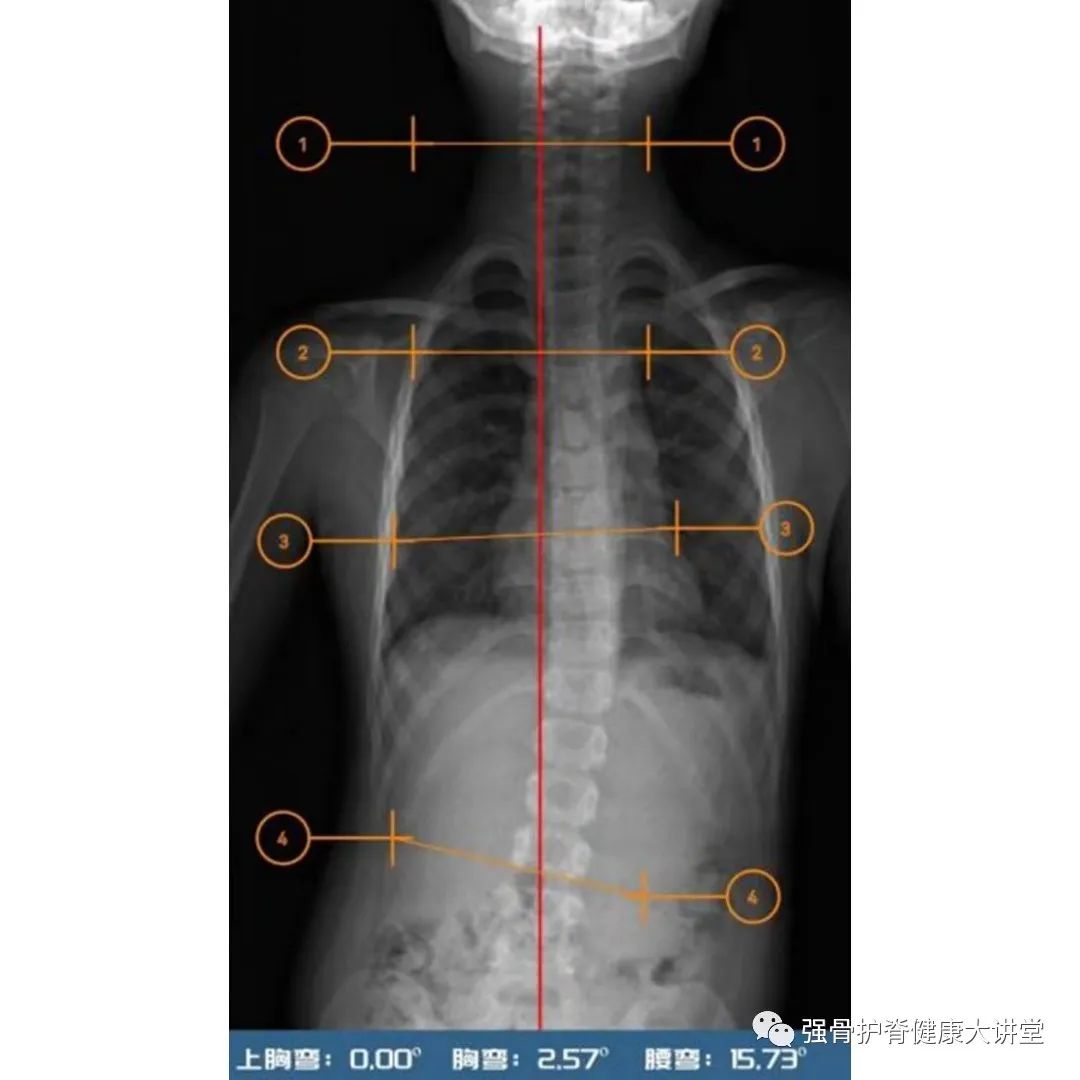

佳佳小朋友于2021年2月份 发现双肩稍不等高,一侧肩胛骨较突出 ,于我院门诊就诊后发现为 轻度青少年特发性脊柱侧弯(Cobb角15.7°) ,在江晓兵教授建议下参加强骨护脊侧弯运动训练营,学习侧弯矫正动作,并嘱咐小朋友回家日常练习,多参与游泳、拉单杠等运动。2022年5月15日,患者行EOS检查后提示 Cobb角(T12/L4)8° ,根据脊柱侧弯临床诊疗标准(患者全脊柱影像片显示脊柱偏离中心线的角度大于10°,即Cobb角大于10°时,可认定为脊柱侧弯),可视为临床治愈。

治疗前全脊柱X光

一年后复查全脊柱影像